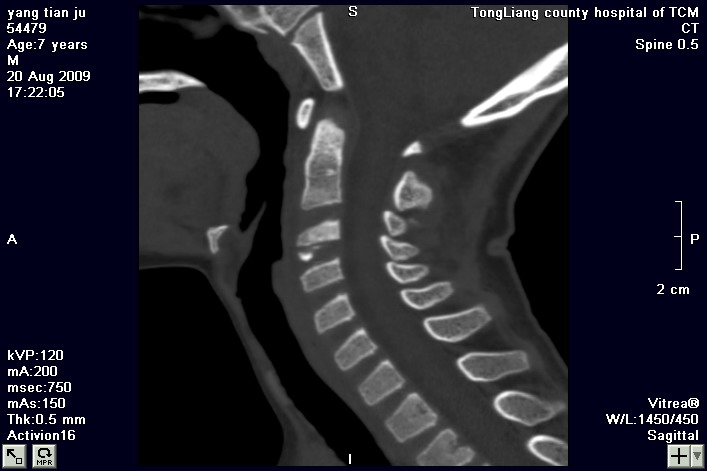

标题: PED2853:颈3/4椎间盘内高密度钙化灶,请各位会诊. [打印本页]

标题: PED2853:颈3/4椎间盘内高密度钙化灶,请各位会诊.

患儿,7岁,颈部疼痛3天,颈部活动受限.

本例应该是典型的儿童钙化性椎间盘病。

儿童钙化性椎间盘病发病年龄多在5~12岁,男女比例相当,大多数患儿发病主要表现为颈部疼痛,伴活动受限。少数有吞咽不适或肢体瘫痪。有一部分患儿无症状,是在其它检查时发现。病因尚不完全明了,可能的有:1、感染。2外伤。

儿童颈椎椎间盘钙化系一良性自限性疾病,可见于颈、胸、腰椎,以颈椎为多发,腰椎少见,多为单发。钙化位于髓核,也可累及软骨板和纤维环引起钙化主要发生于c 4~7  的髓核位于椎间隙正中或偏后,少数向前疝出,以后部多见,呈梭状、盘状、团块状或半环状;(2)颈椎生理曲度变直,椎间隙正常或增宽;(3)相邻椎体可变扁,局部凹陷变形,椎体前下缘鸟嘴状增生,或呈钳口状改变,椎前软组织增厚及环枢椎半脱位;(4)ct可清晰显示椎间盘髓核 位置的钙化灶及经破裂的纤维环向椎管内突出。(5)mri,钙化在t1及t2加权像上均呈低信号,并可见脊髓组织内异常信号。